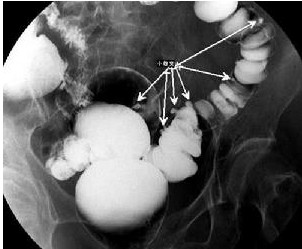

憩室是指肠粘膜经肠壁肌层缺损处向外形成囊状突出的病理结构。多个憩室的存在则称之为结肠憩室病。如果憩室颈部狭小,又与肠壁成锐角,食管(或肠道)内容物一旦进入其中,常可刺激产生炎症,此为急性憩室炎。憩室炎随所在的部位而症状有所差异:食管憩室炎可出现餐后上腹或下胸部胀痛恶心呕吐;在某一特殊体味时,上述症状可缓解。十二指肠憩室炎可引起类似溃疡病症状,饱餐后加重,嗳气呕吐后减轻。结肠憩室炎时可有下腹轻度不适、发胀、阵发性绞痛便秘腹泻交替。乙状结肠憩室炎可有黏液便,酷似阑尾炎,容易误诊。

憩室绝大多数为后天形成的,多位于乙状结肠盲肠升结肠也不少见。

憩室炎的诊断,除了临床症状、体征之外,常需要结核必要的特殊检查。首先是确定憩室的存在,主要依靠消化道钡餐造影钡剂灌肠,上消化道应首选前者而结肠则首选后者。其阳性率明显高于胃肠镜。但在鉴别憩室与结肠癌溃疡性结肠炎克隆恩病阿米巴肠病放射性肠炎等疾病时,肠镜检查仍有重要价值。然而,急性憩室炎时肠镜检查时禁忌症,因为可能引起肠穿孔。消化道出血是否由憩室炎所致,诊断书困难较大,可能需要做选择性动脉造影胶囊胃镜。